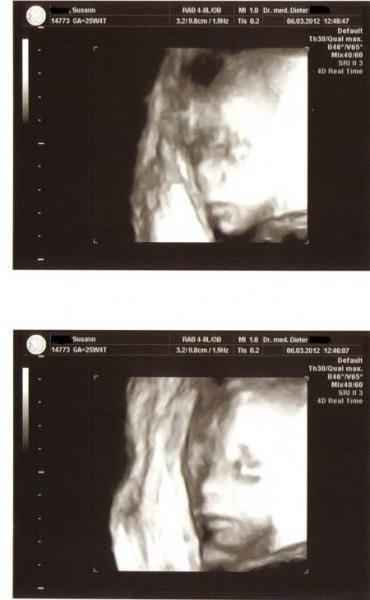

Also es ist alles in Ordnung es war so wunderschön 30 ganze Minuten BabyTv . Es bleibt bei einem Prinzen er ist ca 32 cm Große und 604 Gramm "leicht". er wollte sich nicht so zeigen wie er sollte aber am Anfang haben wir ein schönes Bild hinbekommen. Ich bin noch mehr Verliebt als Vorher so hänge euch noch Bilder ran lg

Bild zu Bericht + Bilder vom 3 D - Forum für Juni - Mamis